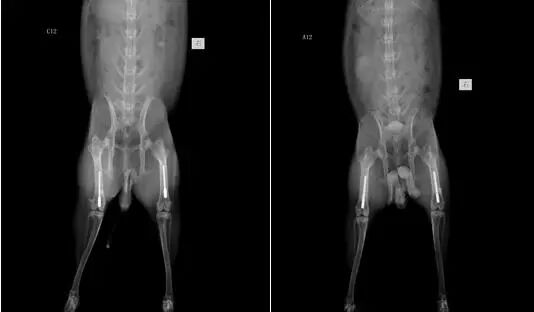

股骨植入

M

i

c

r

o-

CT